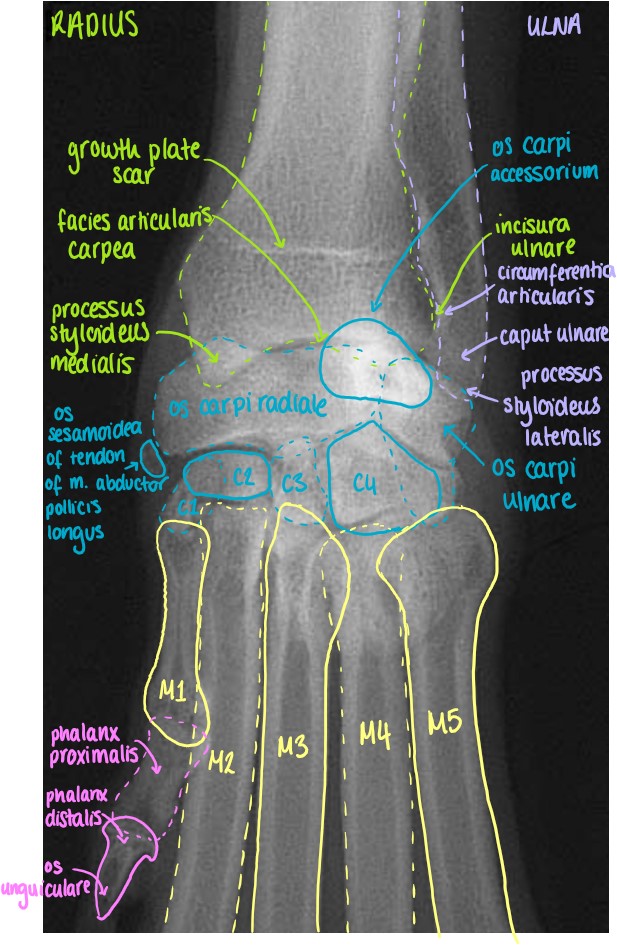

Articulatio Carpi